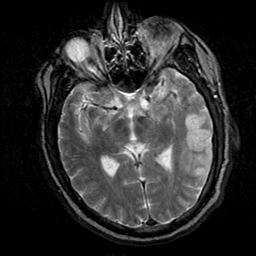

Subacute Stroke, overlay -- Slice #11

[Home][Help][Clinical] Slice 11